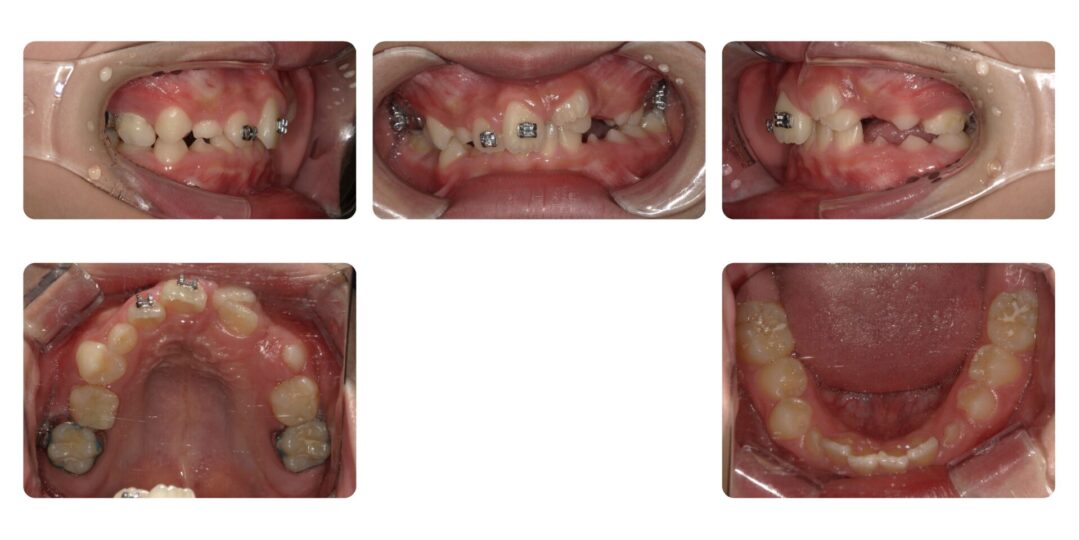

第二期矯正治療前

治療内容

第一期治療 上顎マルチブラケット装置

第二期治療 上顎左右4番抜歯 マルチブラケット装置

治療期間

4年6ヶ月